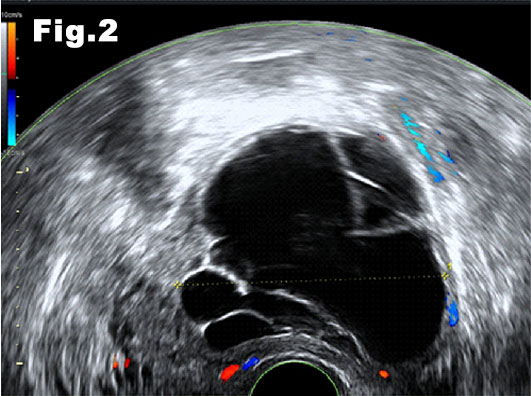

The uterine multilocular cyst was avascular on Doppler examination and maximal diameter was 8cm (fig.2). The septations were thick and fibrotic, as well as avascular. The fluid was anechoic and there were no papillary projections.

Figure 2: Transvaginal scan ,transverse view. Lesion-measuring 80mm. Normal myometrium (white arrow) on the right.

![Cystic fibroids</br> [Feb 2017]](http://s834315022.websitehome.co.uk/wp-content/uploads/2020/11/cotm-feb2017-fig2.jpg)